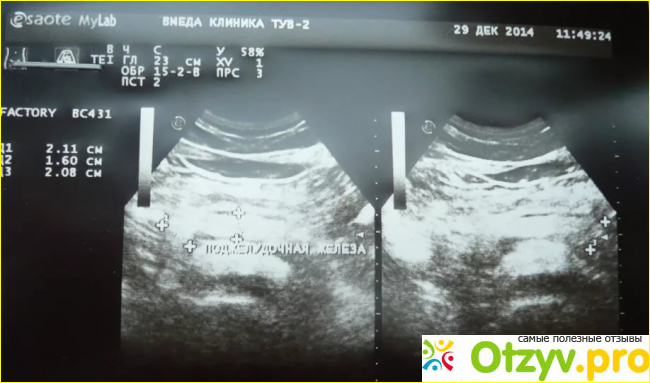

Ультразвуковое исследование действительно может пролить свет на те или иные проблемы со здоровьем, а посему его прохождение обычно настоятельно рекомендуется лечащими врачами. Гастроэнтерологическое УЗИ включает в себя обычно исследование такие органов человеческого организма, как печень, желчный пузырь, и поджелудочная железа.

В результате подобного исследования определяются размеры органов желудочно-кишечного тракта, а также проверяется их работоспособность, как, например, желчного пузыря.